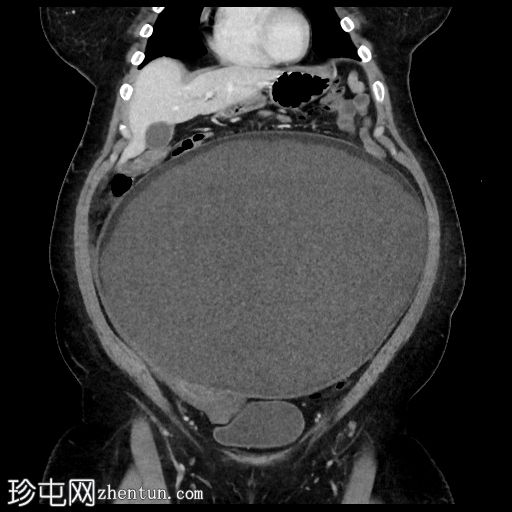

轴位增强扫描(门静脉期)

盆腹腔巨大囊性病变,可见脂肪液平面及漂浮球征(脂肪/软组织团块漂浮)

病变周边可见钙化灶

左侧附件呈旋涡状外观,提示附件扭转

以上影像学表现提示左侧卵巢成熟囊性畸胎瘤伴附件扭转

右侧附件病变主要由脂肪组成,伴钙化及软组织成分